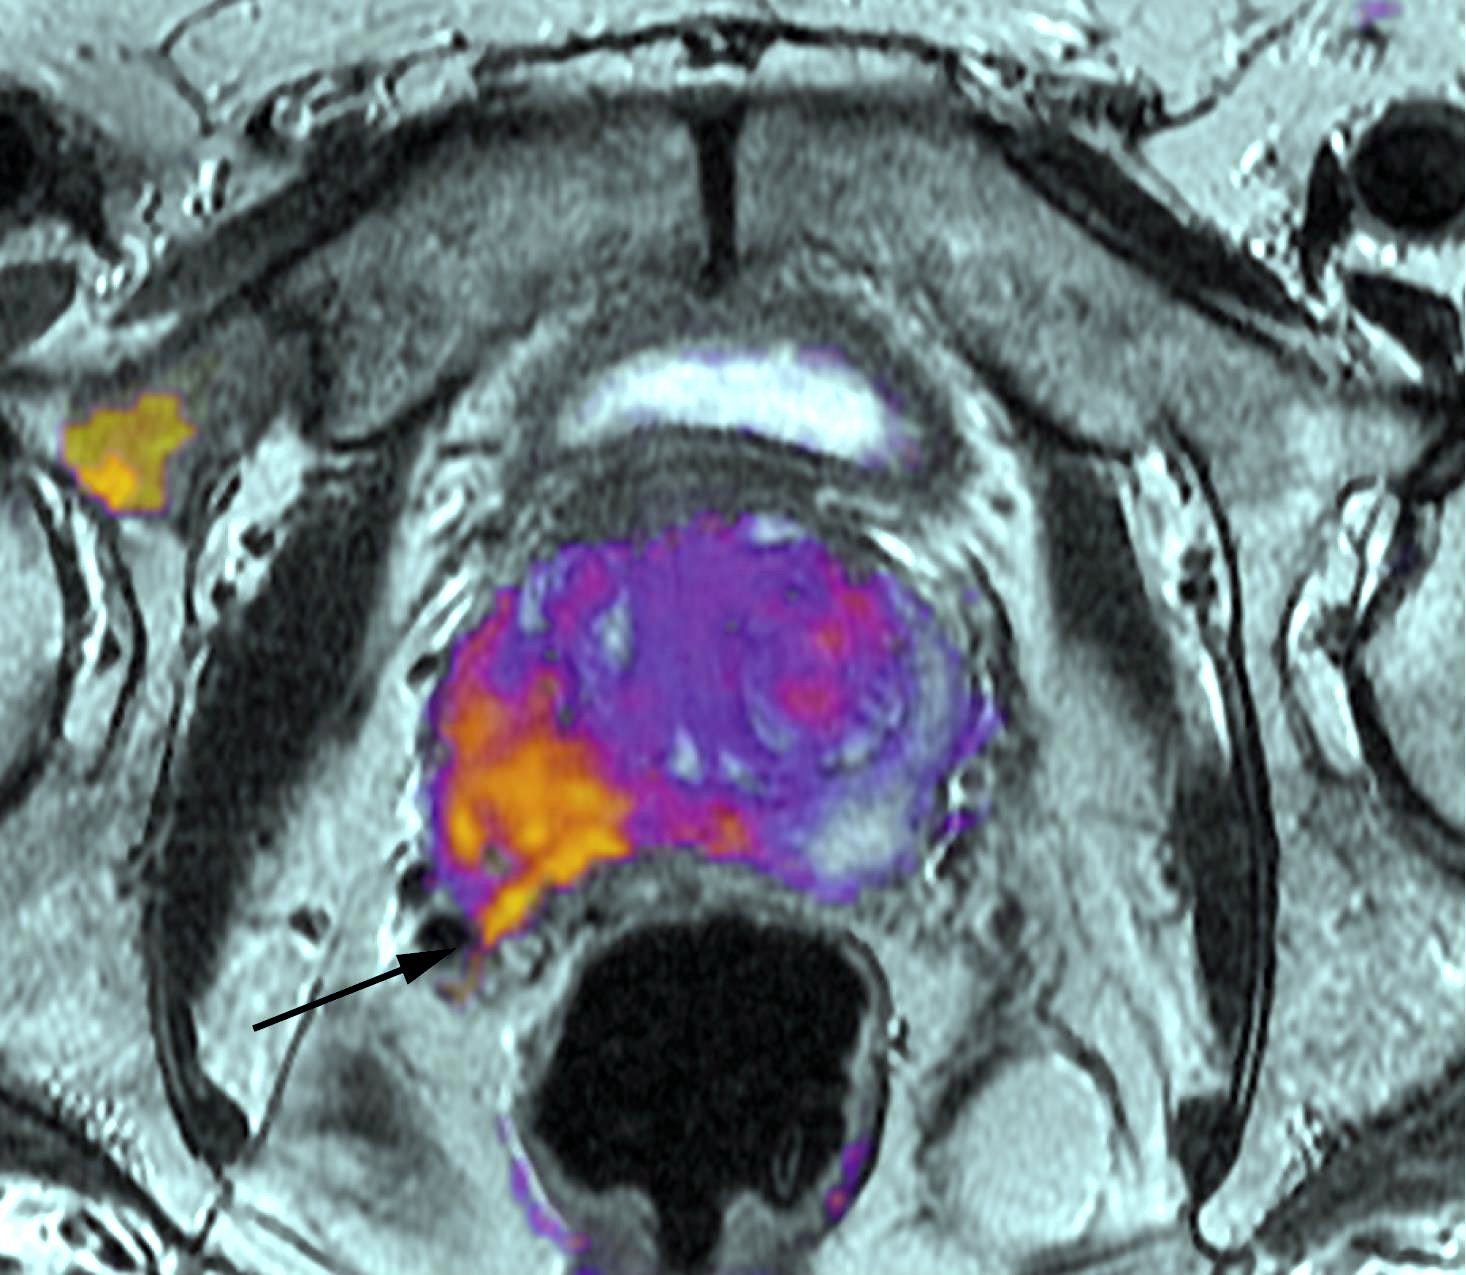

Riesgo de enfermedad cardiovascular y terapia de privación de andrógenos en pacientes con cáncer de próstata localizado: un estudio prospectivo de cohorte

British Journal of Cancer, noviembre de 2017 En hombres con cáncer de próstata clínicamente localizado que se encontraban inicialmente bajo vigilancia activa, la TPA se asoció con un mayor riesgo de insuficiencia cardíaca en hombres sin ninguna ECV preexistente. También un mayor riesgo de arritmias y trastornos de la conducción en hombres con ECV preexistente. Este estudio proporciona la base para identificar a los hombres de alto riesgo tratados con TPA que podrían beneficiarse con el monitoreo cardíaco regular y las recomendaciones de modificación del estilo de vida.